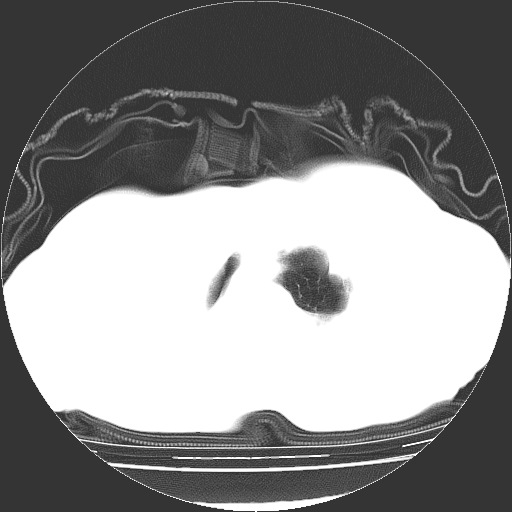

标题: CT23991:女,72岁,咳嗽、憋气一周。 [打印本页]

女,72岁,咳嗽、憋气一周,十年前曾患肺结核及胸膜结核。

右侧毁损肺,右侧纵隔疝

右侧毁损肺,右侧纵隔疝,左肺代偿!

1.右侧损毁肺伴胸膜钙化,2.左肺小结节灶,良性可能大,注意复查。3.肝脏左叶囊肿。4.先天性一侧肺不发育待出外(右侧胸廓无明显塌陷)。对比原片应该非常有帮助。

右侧肺毁损,左肺代偿性肺气肿,纵隔疝。